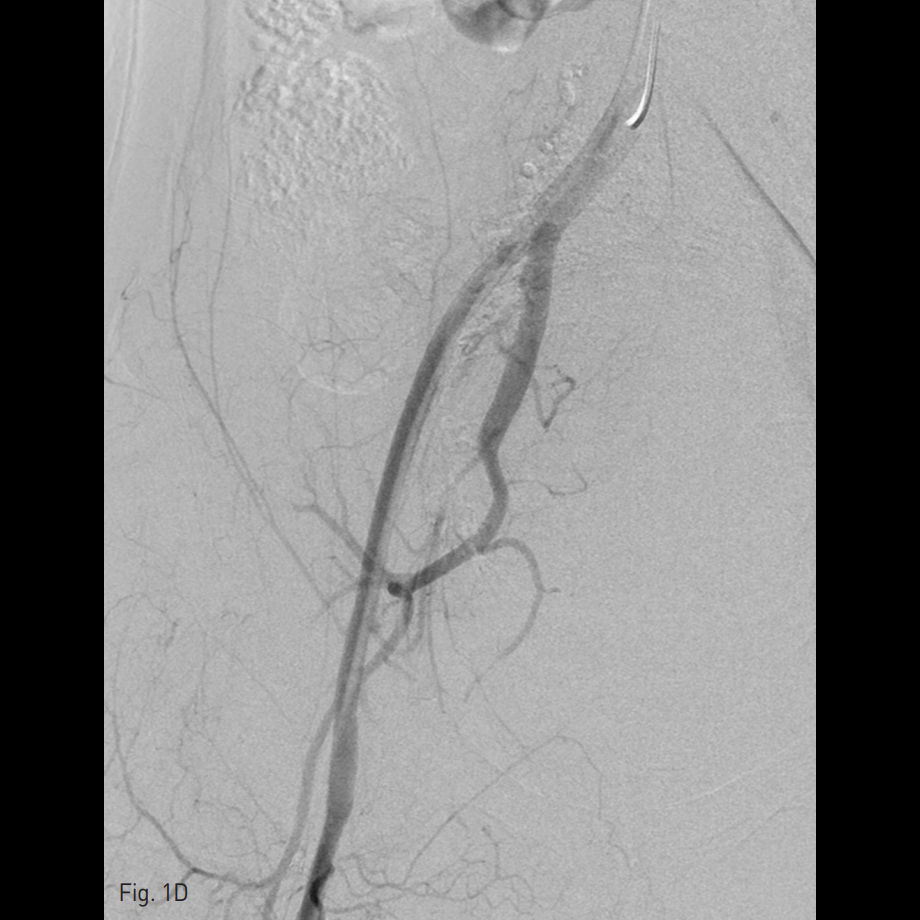

우측 총대퇴동맥을 천자하여 5 Fr sheath를 삽입하고, 5 Fr RUC catheter (Roberts Uterine Catheter, COOK medical, Bloomington, IN, USA)를 이용하여 좌측 내측 장골동맥을 선택하여 조영술을 시행한 뒤 좌측 자궁동맥을 선택하여 조영술 시행하였으며 (Fig. 1A), 출혈의심소견이 있어 gelfoam을 이용하여 색전술을 시행하였다 (Fig. 1B). 이후에 시행한 우측 내측 장골동맥을 선택하여 조영술을 시행한 뒤 (Fig. 1C), 우측 자궁동맥을 초선택하여 조영술을 시행하였을 때, 우측 자궁동맥이 비후되어 있어, gelfoam을 이용하여 색전술을 시행하였다. 색전술 직후 산부인과 진찰에서 지속적인 출혈소견이 보였다. 이에 5 Fr pigtail catheter를 이용하여, 대동맥 조영술을 시행하였다. 하장간막동맥 (Inferior mesenteric artery)으로 부터 출혈 소견이 관찰되었다 (Fig. 2A). 이에 대해서 2.2 Fr 마이크로카테터 (Progreat, Terumo, Japan)를 이용하여 하장간막동맥을 초선택하여 코일(Nester microcoil, COOK Medical, Bloomington, IN, USA)과 gelfoam (Spongostan, Ferrosan Medical Devices, Denmark)을 이용하여 색전술을 시행하였다 (Fig. 2B). 이후 다시 하장간막동맥 조영술을 시행하여 더 이상의 출혈이 없음을 확인하고 시술을 종료하였다 (Fig. 2C).

Fig. 1

A. Left internal iliac artery angiogram showed hypertrophied and left tortuous uterine artery.